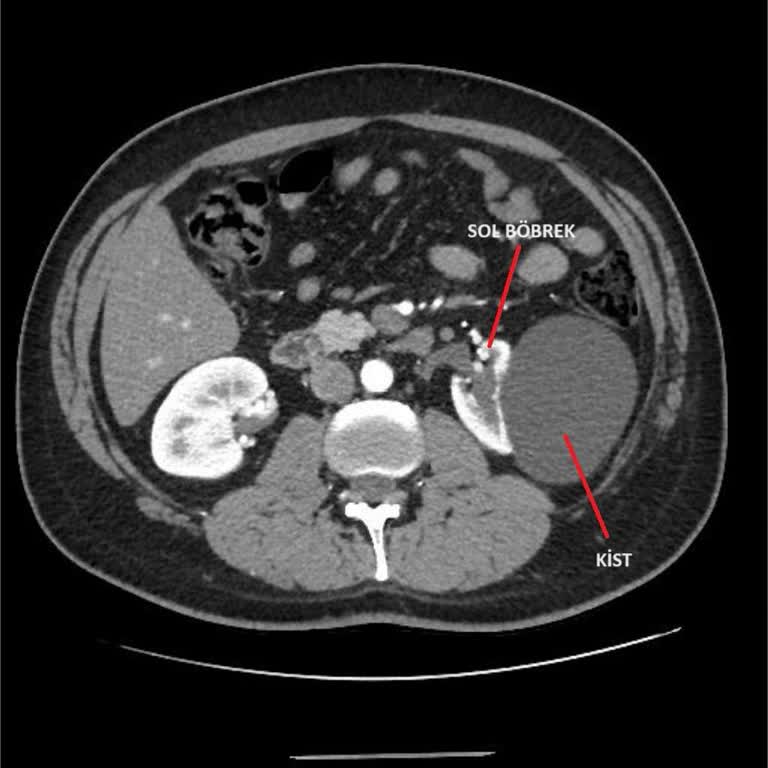

08.01.2026 tarihinde Çekmeköy İlhan Varank Ek Binası KBB bölümüne başvurdum. Doktor muayene sonrasında kan tahlili ve tomografi istedi, sonuçlara göre 09.01.2026 tarihinde yatış verilebileceğini ifade etti. Aynı gün sekreter g*** Hanım, kan sonuçları çıkmadan tomografi çekilemeyeceğini söyleyerek er...